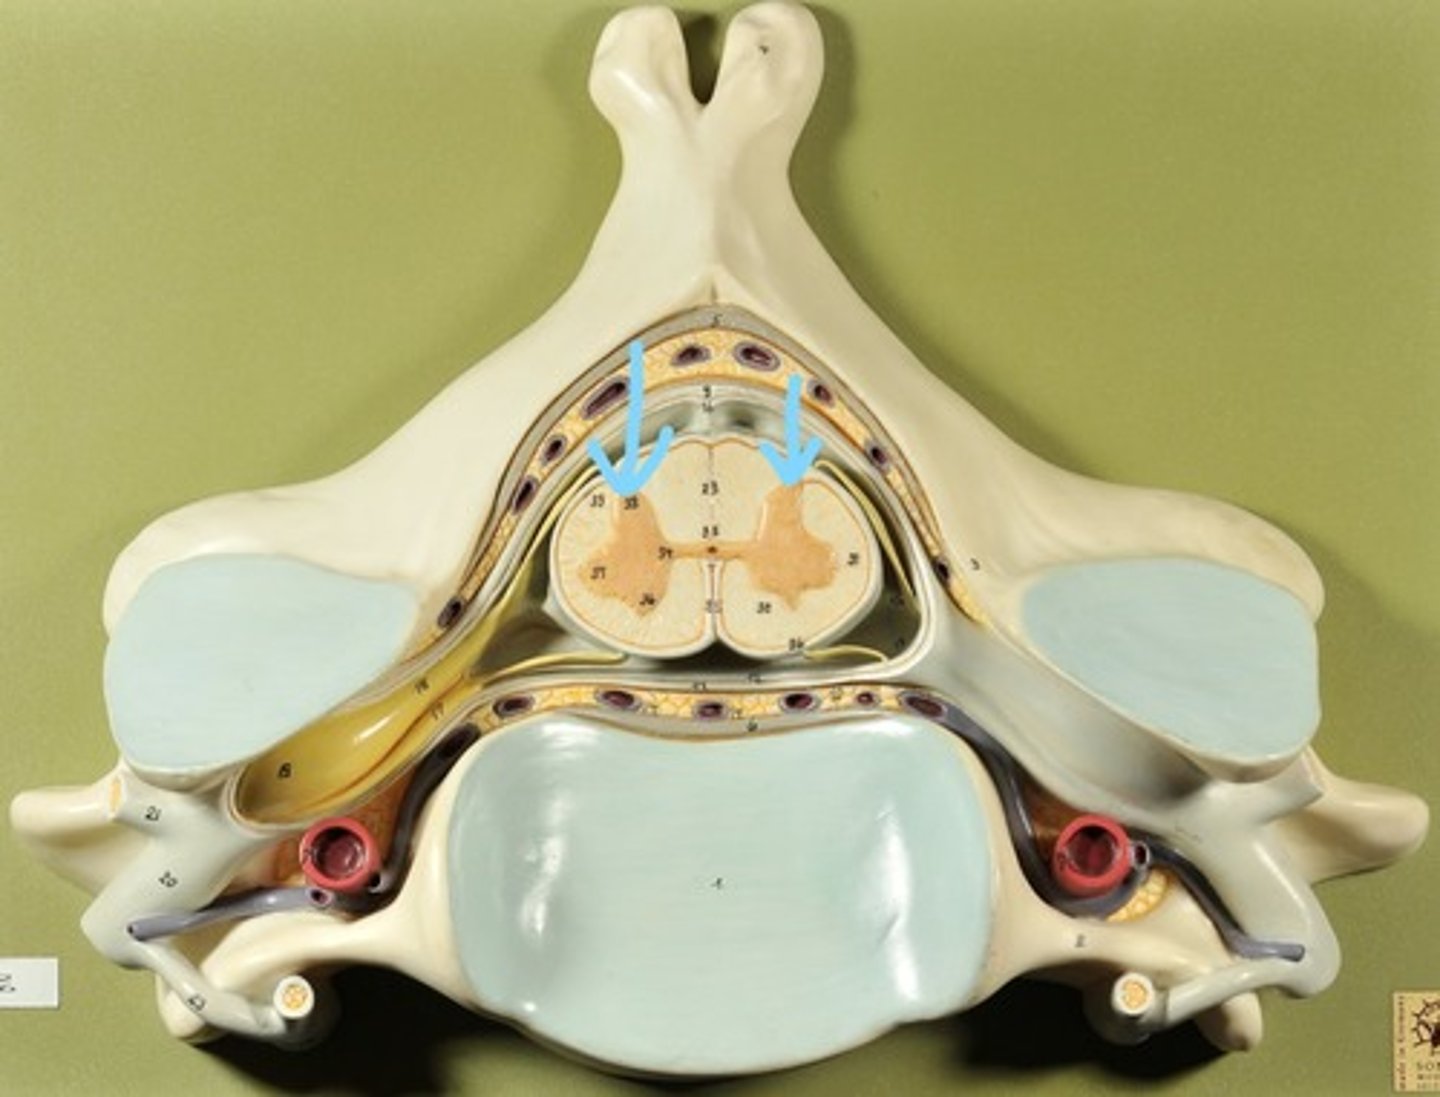

Identify all structures of spinal cord

White Matter of spinal cord

gray matter of spinal cord

Ventral Horns (gray matter)

Lateral Horns (gray matter)

Dorsal horns (gray matter)

Anterior Columns (white matter)

Lateral Columns (white matter)

Posterior Column (white matter)

central canal of spinal cord

Identify all structures

Pia Mater

Subarachnoid Space

Arachnoid mater

Subdural Space (brown line)

Dura mater

Epidural Space

Dorsal Root Ganglion

Dorsal Root

Ventral Root

Spinal Nerve